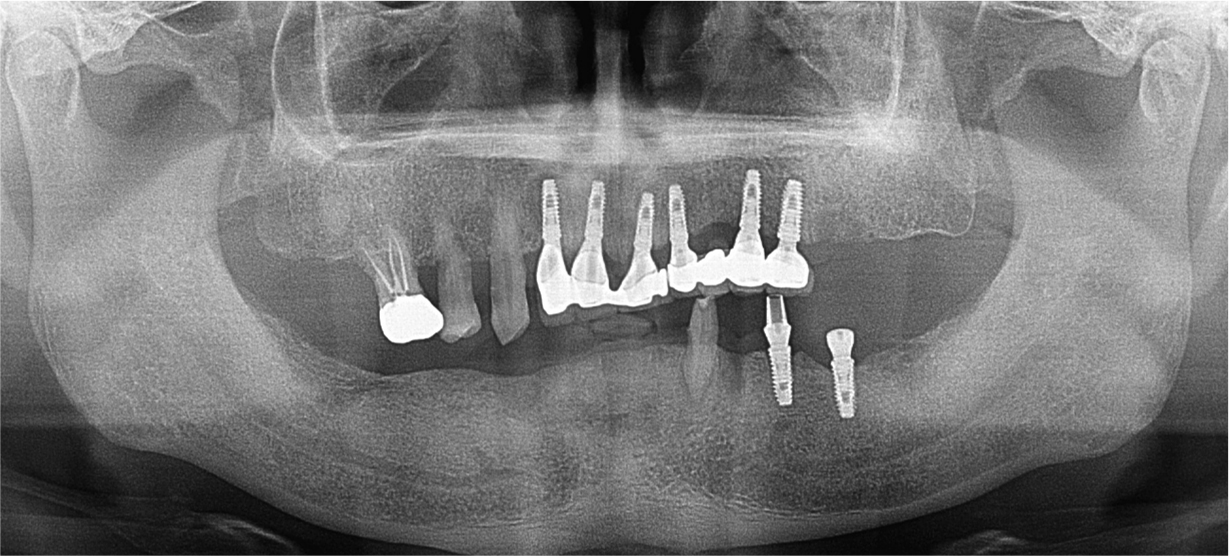

A 58-year-old male patient visited our hospital with chief complaints of missing mandibular teeth. The patient had hypertension and hyperlipidemia. Clinical and radiological examinations revealed multiple tooth loss in the mandible and canting of the maxillary teeth. The implant in the lower left second premolar area showed degree II mobility and vertical bone loss around the fixture, indicating a loss of osseointegration (Figs. 1 and 2). After removal of the dental implant on #35, implant placement was planned at sites #47, 46, 44, 43, 32, 33, 34, 36, and 37. The patient refused to undergo temporary denture placement. A radiographic stent was fabricated after bite registration using a record base, which is the conventional method for fabricating a stent in a partially edentulous jaw. CBCT was taken, and the stone model was scanned using an optical scanner (Medit T500 Dental 3D Scanner; Medit Corp., Seoul, Korea) (Fig. 3A).